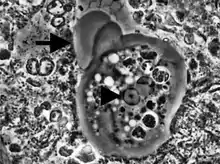

Entamoeba gingivalis apatojen bir protozoondur (Hastalık oluşturduğu da bildirilmiştir). İnsanda yerleştiği bildirilen ilk amip türüdür. Genellikle ağızda gingival ceplerde ve diş etrafındaki dokularda yerleşir. Gingivit ve periodontit olana hastalarda sık gözlenir fakat oral hijyen önemlidir. Kist formu yoktur. Öpüşme veya aynı beslenme araçlarını kullanma yoluyla insandan insana bulaşabilir. Yalnızca 10-35 boyutlarında trofozoit formu vardır. Yuvarlak çekirdeği 2-4 mikrometre çapındadır ve merkezi bit endozomu vardır. Pseudopodları ile hızlıca yer değiştirebilir. Stoplazmasında çok sayıda besin vakoülü içerir. Besin atıklarını, bakterileri, kan hücrelerini fagosite edebilir.